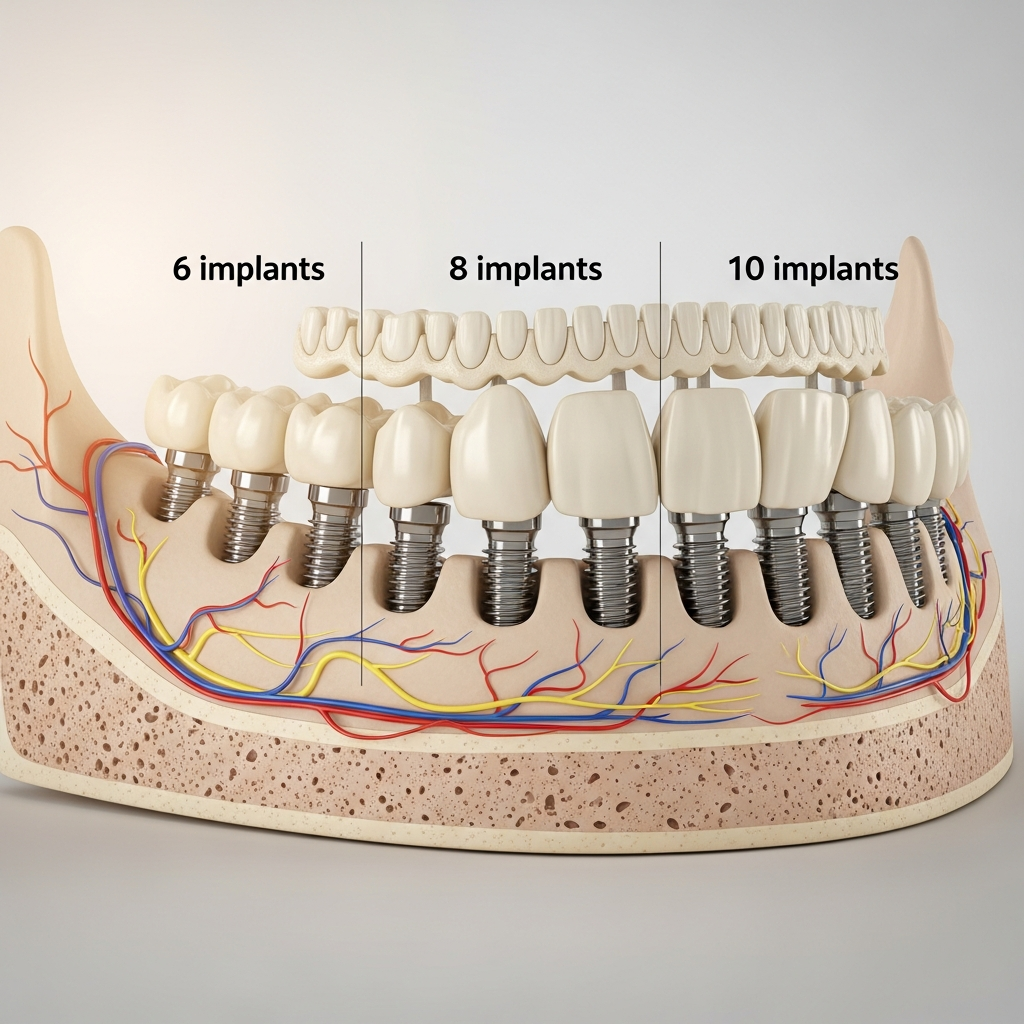

Ghid alegere implanturi bazale: 6 vs 8 vs 10 pentru rezultatul perfect

Alegerea diametrului (6, 8 sau 10 mm) se face în funcție de anatomie și sarcină:

- Implant 6 mm: Indicat în zone cu spațiu limitat (de ex., zona frontală), unde grosimea osoasă este modestă. Oferă o rezistență adecvată pentru dinți uniradiculari.

- Implant 8 mm: Diametrul cel mai versatil și frecvent utilizat. Potrivit pentru majoritatea zonei molare și premolare, oferind un echilibru optim între rezistență și conservarea structurii osoase.

- Implant 10 mm: Rezervat pentru situații cu deficit osoos sever în înălțime, dar cu lățime suficientă. Asigură o suprafață de contact maximă cu osul cortical și este adesea folosit pentru reabilitări complexe cu arcadă completă.

Datele recente (2025-2026) subliniază că succesul pe termen lung al implanturilor bazale depinde în primul rând de o selecție riguroasă a diametrului, adaptată la anatomia individuală și de o planificare 3D meticuloasă. Nu există un diametru „perfect” universal; alegerea între 6, 8 sau 10 mm este o decizie terapeutică bazată pe dovezi imagistice și pe principii biomecanice. Eficacitatea este maximă atunci când tehnica se alătură indicației corecte.